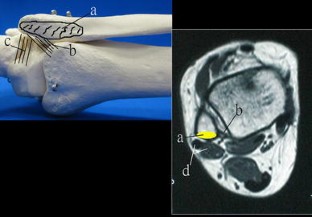

Fig. 1

Fig. 2

Fig. 3